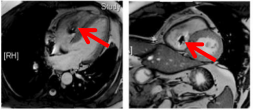

另外,即使是MRI兼容的心脏起搏器,在进行心脏检查时依旧会有伪影,影响检查结果。